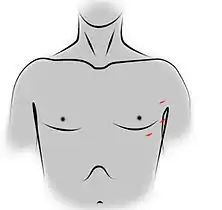

- Voies d'abord utilisées

Incision de sternotomie médiane pour une thymectomie trans-sternale. Incisions des orifices de trocarts pour une thymectomie vidéo-assistée par voie gauche.

Incisions des orifices de trocarts pour une thymectomie vidéo-assistée par voie gauche. Incision de cervicotomie pour une thymectomie trans-cervicale.

La voie vidéothoracoscopique et la voie robotique sont très similaires[76], la chirurgie assistée par robot étant un prolongement technologique de la chirurgie vidéo où l'opérateur gagne simplement des degrés de liberté au niveau de la manipulation des instruments, qui se fait à partir d'une console située dans la salle d'intervention. Plutôt qu'à travers le sternum, le thymus est abordé par l'une des cavités pleurales. Un abord vidéothoracoscopique nécessite donc une ventilation unipulmonaire afin de dégager un espace de travail suffisant (dans le cas contraire, le poumon gonflé d'air occupe toute la cavité pleurale et empêche le passage des instruments)[76]. La ventilation sur un seul poumon est permise par une intubation sélective lors de l'anesthésie. Par ailleurs, l'insufflation à faible pression de CO2 peut faciliter tant l'exposition que la dissection des structures en achevant de repousser le poumon loin de la zone de travail[85].